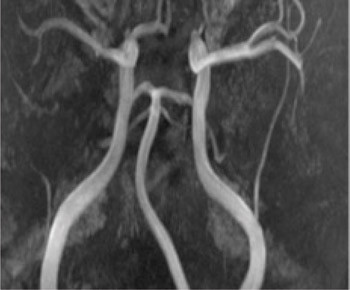

En person i 20-årene med kjent migrene med aura fikk infarkter i høyre arteria cerebri media og begge anteriorgebet (figur 1 viser en magnettomografidiffusjonsvektet serie). Cerebral computer- og magnettomografi med blodstrømsangiografi (MRA) etter innleggelse viste upåfallende strømning uten tegn til disseksjon eller vaskulitt. Hemikraniektomi ble nødvendig etter utvikling av malignt hjerneødem. MR-angiografi i narkose dagen etter operasjonen viste åpne arterier (figur 2 viser en åpen carotistopp (hvit pil), normal basilaristopp (rød pil) samt en ikke-lukket Willis’ sirkel, som er en anatomisk normalvariant (stjerner)). Testing på sentralstimulerende substanser, antikardiolipin, antinukleære antistoffer, nevronantistoffer og tumormarkører ga negative funn. Transøsofageal ekkokardiografi viste et minimalt patent foramen ovale, lite sannsynlig relatert til hendelsen, ifølge kardiolog. Pasienten utviklet alvorlig hjernestammeaffeksjon og MR-angiografi viste forsnevring i arteria basilaris posterior-forgreningen (pilene i figur 3). Arterielle karspasmer ble retrospektivt mistenkt. Den første mistenkte karspasmen i høyre media-/anteriorforgreningen forble udokumentert. Den andre i basilaris-/posteriorforgreningen ble dokumentert postoperativt (pilene i figur 3). Bildene av flere nytilkomne infarkter i bakre kretsløp vises ikke. Tre uker etter hemikraniektomi var ny angiografi normalisert (figur 4).